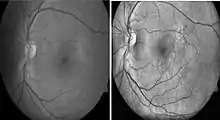

Diabetic retinopathy

Diabetic retinopathy is a disease of the retina that is diagnosed predominantly by fundoscopic images. Diabetic patients in industrialised countries generally undergo regular screening for the condition. Imaging is used to recognize early signs of abnormal retinal blood vessels. Manual analysis of these images can be time-consuming and unreliable.[75][76] CAD has been employed to enhance the accuracy, sensitivity, and specificity of automated detection method. The use of some CAD systems to replace human graders can be safe and cost effective.[76]

Histogram Equalization Sample Image. Left: Normal gray-scale fundoscopic image. Right: Post-histogram equalization processing.[79]

Histogram equalization is useful in enhancing contrast within an image. This technique is used to increase local contrast. At the end of the processing, areas that were dark in the input image would be brightened, greatly enhancing the contrast among the features present in the area. On the other hand, brighter areas in the input image would remain bright or be reduced in brightness to equalize with the other areas in the image. Besides vessel segmentation, other features related to diabetic retinopathy can be further separated by using this pre-processing technique. Microaneurysm and hemorrhages are red lesions, whereas exudates are yellow spots. Increasing contrast between these two groups allow better visualization of lesions on images. With this technique, 2014 review found that 10 out of the 14 recently (since 2011) published primary research.[77]